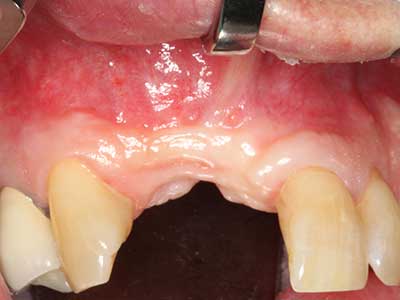

Фиг. 2: Хоризонтален и вертикален латерално-максиларен дефект с висока линия на усмивката с индикация за пре-реконструкция за имплант.

Фиг. 6: След препарация на мукопериосталната клапа.